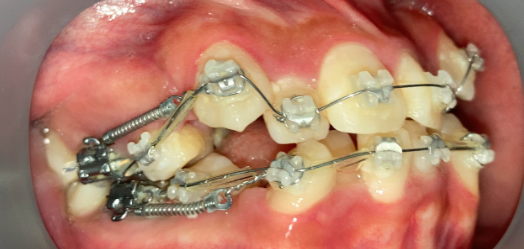

症例:非抜歯+アンカーで改善したケース

症例:ガタガタ+軽度の口元突出 → 非抜歯+アンカーで改善

非抜歯アンカー矯正の初診時|奈良の矯正歯科

初診時

インプラントアンカー装着中の矯正治療経過|奈良の矯正歯科

アンカー装着中

インプラントアンカーで上の歯列全体を後方に移動。抜歯せずにガタガタと口元の突出感を改善しました。

ℹ️ ただし、この方法には限界があります。歯を後ろに動かせる量には上限があるため、口元の突出が大きい場合やガタガタが重度の場合は、非抜歯では対応できません。適応かどうかは精密検査で判断します。